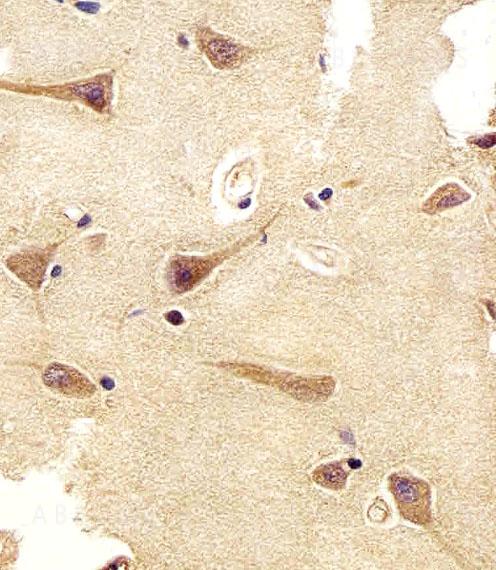

Figure 1: Immunohistochemical analysis of paraffin-embedded h brain section using UCHL1 Antibody (10-6599). UCHL1 Antibody was diluted at 1:25 dilution. A undiluted biotinylated goat polyvalent antibody was used as the secondary, followed by DAB staining.